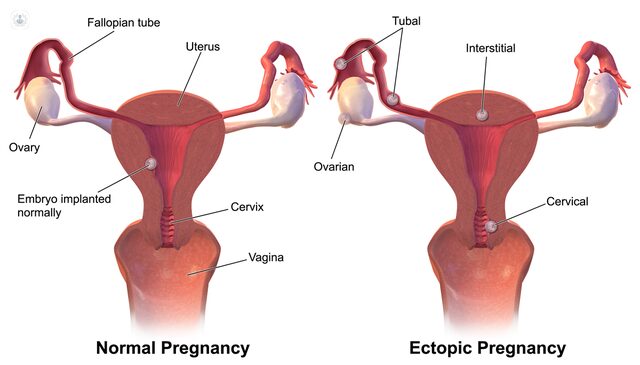

يحدث الحمل في قناة فالوب لدى بعض النساء، ويشكل خطرًا كبيرًا على حياتهن إذا لم يتم اكتشافه مبكرًا. يحدث ذلك عندما يتم تشكيل الجنين في قناة فالوب بدلًا من الرحم.

يحدث الحمل خارج الرحم عندما تنمو البويضة المخصبة في مكان غير الرحم، وغالبًا ما تزرع البويضة في قناة فالوب التي تشكل ممرًا صغيرًا يمر من خلاله البويضة المخصبة للوصول إلى الرحم.

وإذا استمر الحمل خارج الرحم ولم يتم اكتشافه، فإن الجنين ينمو ويصبح كبيرًا جدًا بالنسبة لحجم قناة فالوب، مما يؤدي إلى تمزقها وتعريض حياة الأم للخطر.